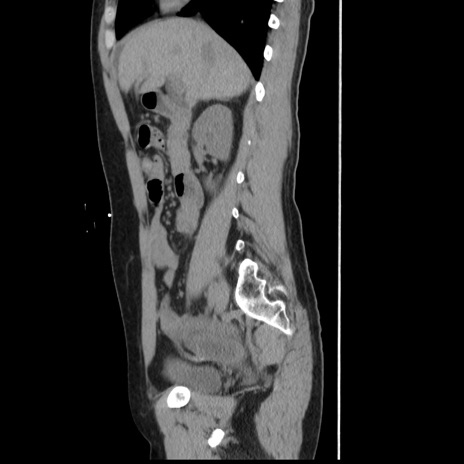

症例10(矢状断像)

【症例】 50歳代女性

【主訴】 腹痛

【現病歴】前日生レバーを食べた。今朝に排便あり。 昼前に突然発症の腹痛を生じ、当院救急外来を受診した。

【既往歴】 子宮筋腫にてで子宮全摘後

【身体所見】 意識清明、腹部:平坦、軟、下腹部やや左を中心に圧痛・反跳痛あり、筋性防御あり

【データ】WBC 7800、CRP 0.07